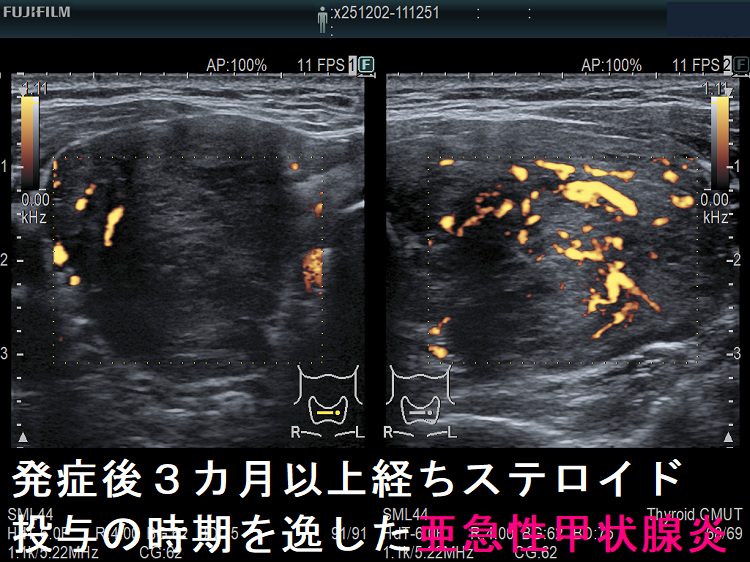

- 発症後数か月以上経ち、ステロイド投与の時期を逸した場合